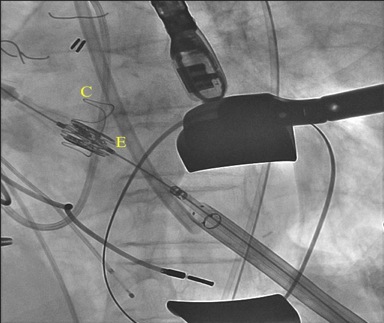

During the 16-hour duration of her evaluation, her creatinine level rapidly rose to 1.6 mg/dL, and she became anuric. This change in clinical course, combined with the perinephric fluid collection, raised concern for obstruction with a perinephric urinoma. She was taken to the operating room urgently for stent placement and retrograde pyelography, which showed a long segment of narrowed proximal ureter entering an entirely intrarenal pelvis. A wisp of contrast laterally suggested a forniceal rupture (Figure 3). After stent insertion, the girl developed significant postobstructive diuresis of greater than 9 mL/kg/h; ultimately, her creatinine level returned to a baseline of 0.4 mg/dL.